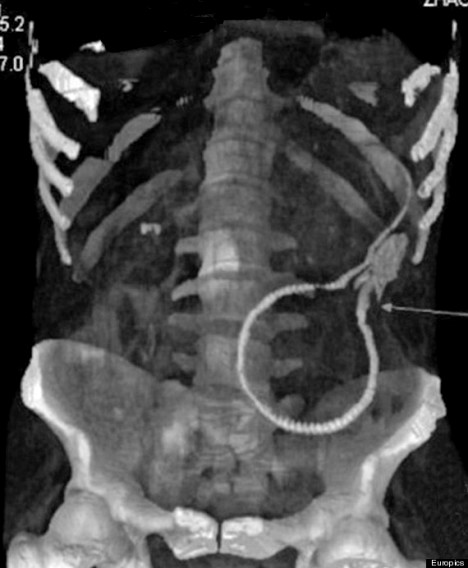

cocaine

CAT SCAN: In this Monday Sept. 12, 2011 image of a CAT scan released by Brazilian Federal Police on Sept. 16, 2011, bags loaded with cocaine are seen inside the body of an unidentified man after he was arrested at the Congonhas airport in Sao Paulo, Brazil on Monday. According to a federal police press release, the man is identified as a young Irish male who tried to board a flight to Brussels after swallowing 72 capsules containing a total of 830 grams.